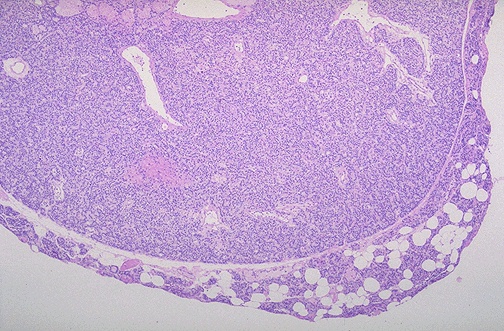

Image 2.2

The lesion is circumscribed. Describe the histologic findings.